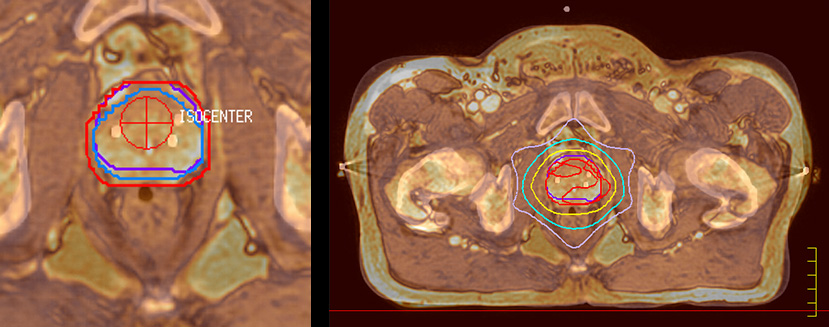

“The biggest problem for CT-based planning, especially in prostate, is you can’t see the cancer very well,” says Dr. Stevens. “On CT it can be quite challenging to see the edge of the prostate especially at the apex. When the edge of the prostate can’t be delineated well on CT, radiation oncologists will increase their margins a little bit so they don’t miss it, but that can also increase toxicity.” “Using MR, the prostate is well delineated. We quickly see the edges of cancerous tumors like in prostate cancer, and as normal structures can be defined, we can optimize the treatment plan to protect these organs and their normal function. This can potentially improve the outcome. And it improves workflow as well. We can contour more quickly, confident that the tumor is going to be in the field.” “The Ingenia 3.0T MR scanner provides high resolution allowing us to make scans fast for the patients. It also gives the potential to include methods like MR spectroscopy and diffusion weighted Imaging, which we’re in the process of doing right now,” Dr. Stevens adds.

“There are some general challenges in RT imaging – even with CT – such as imaging geometry and positioning accuracy. Positioning is extremely important in RT, because we need reproducibility between imaging and treatment position. We also need accurate geometry so we can be sure our treatment plan is properly delivered during the treatment,” says Dr Yan. “The Ingenia MR-RT configuration includes an external laser positioning system for patient alignment and a flat tabletop for imaging the patient in treatment position. Ingenia MR-RT also came with a special QA package for regular monitoring of precision. Our Ingenia 3.0T scanner achieves good geometric accuracy – within a millimeter for most patients – and the phantom measurement is even better,” he adds. “Ingenia’s wide 70 cm bore is valuable to easily accommodate immobilization devices needed in RT,” says Dr. Stevens. “With a small bore MR scanner you can’t get the RT immobilization devices into the scanner properly; the large bore makes it easy to image patients in their immobilization device.”

“When a patient registers, first CT simulation and MR simulation are done, followed by CT-MR registration on Pinnacle3. Then the target and normal organ delineation is performed on MR images. Meanwhile we create a reference CT image for online treatment and localization correction. During the treatment phase we can perform additional MRI scans to visualize the anatomy changes and create an adaptive plan. This plan basically adapts the treatment plan to the changes.” “Along with its great benefits, MR has introduced some new challenges,” Dr. Stevens says. “Radiation therapy teams generally have no experience with MR. The Philips training helped us to implement fully the things we can do with the Ingenia MR-RT system. So the training, as well as having a good MR physicist, is critical.”